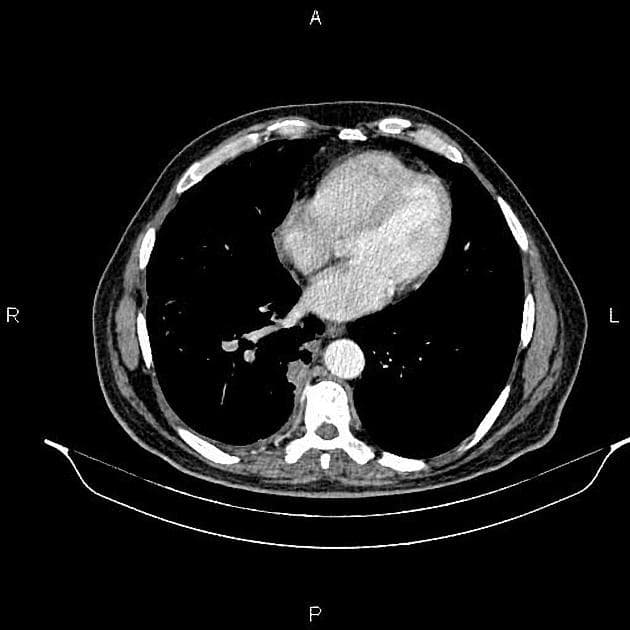

CT

CT là phương tiện hình ảnh chính ("workhorse") để đánh giá tụy:

đánh giá khả năng cắt bỏ

CT tương quan tốt với các phát hiện phẫu thuật trong dự đoán không thể cắt bỏ (giá trị dự đoán dương: 89-100%) ref

đặc điểm chính là mối quan hệ của khối u với các mạch máu xung quanh:

bao quanh động mạch mạc treo tràng trên và trục tạng >180 độ được phân loại là bệnh lý T4, cho thấy không thể cắt bỏ ref